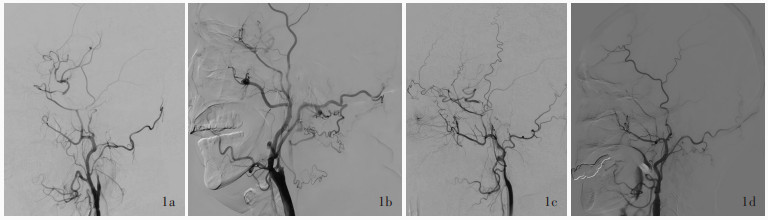

Jiang WJ , Liu AF , Yu W , Qiu HC , Zhang YQ , Liu F , Li C , Wang R , Zhao YL , Lv J , Li TX , Liu C , Zhou J , Zhao JZ . Outcomes of Multimodality In situ Recanalization in Hybrid Operating Room (MIRHOR) for symptomatic chronic internal carotid artery occlusions. J Neurointerv Surg, 2019, 11: 825- 832.

|